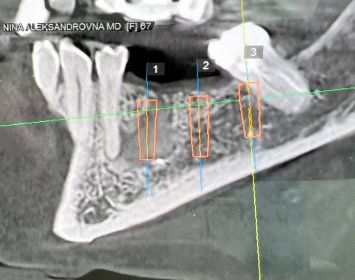

КЛинический случай ильи коробкова

отсроченная ИМПЛАНТАЦИЯ после удаления кисты

Пациентка 65+. Радикулярная киста в области зуба 35.

Удаление зуба с заполнением остаточной полости костным графтом.

Через 6 месяцев установка имплантов VEGA 3,5х12мм.- 2 шт. и 3,5х10мм.

Протезирование через 4 месяца.